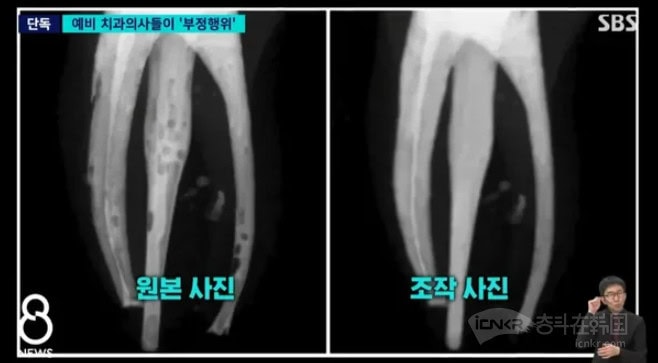

Nel secondo semestre del 2025, durante un corso pratico di terapia endodontica, circa 40-50 studenti hanno riscontrato difficoltà tecniche nell’esecuzione delle otturazioni canalari. Le radiografie mostravano difetti evidenti come spazi vuoti, bolle d’aria e distribuzione irregolare dei materiali riempitivi, elementi fondamentali per valutare la qualità del trattamento. Per mascherare tali imperfezioni, gli studenti hanno utilizzato software di fotoritocco come Photoshop per modificare le immagini, presentando così casi apparentemente perfetti. Alcuni hanno addirittura sostituito completamente le proprie radiografie fallimentari con esempi ideali scaricati da internet.

La frode è stata scoperta grazie all’occhio attento di un docente che ha rilevato anomalie nelle immagini troppo “perfette” e tracce evidenti di editing digitale. L’analisi approfondita delle registrazioni video delle procedure cliniche e dei dati originali ha confermato una discrepanza tra l’effettivo lavoro svolto dagli studenti e le immagini presentate. L’università ha quindi istituito una commissione speciale che ha esaminato tecnicamente tutte le radiografie prodotte dagli oltre 80 partecipanti al corso, rivelando così l’entità collettiva della contraffazione.